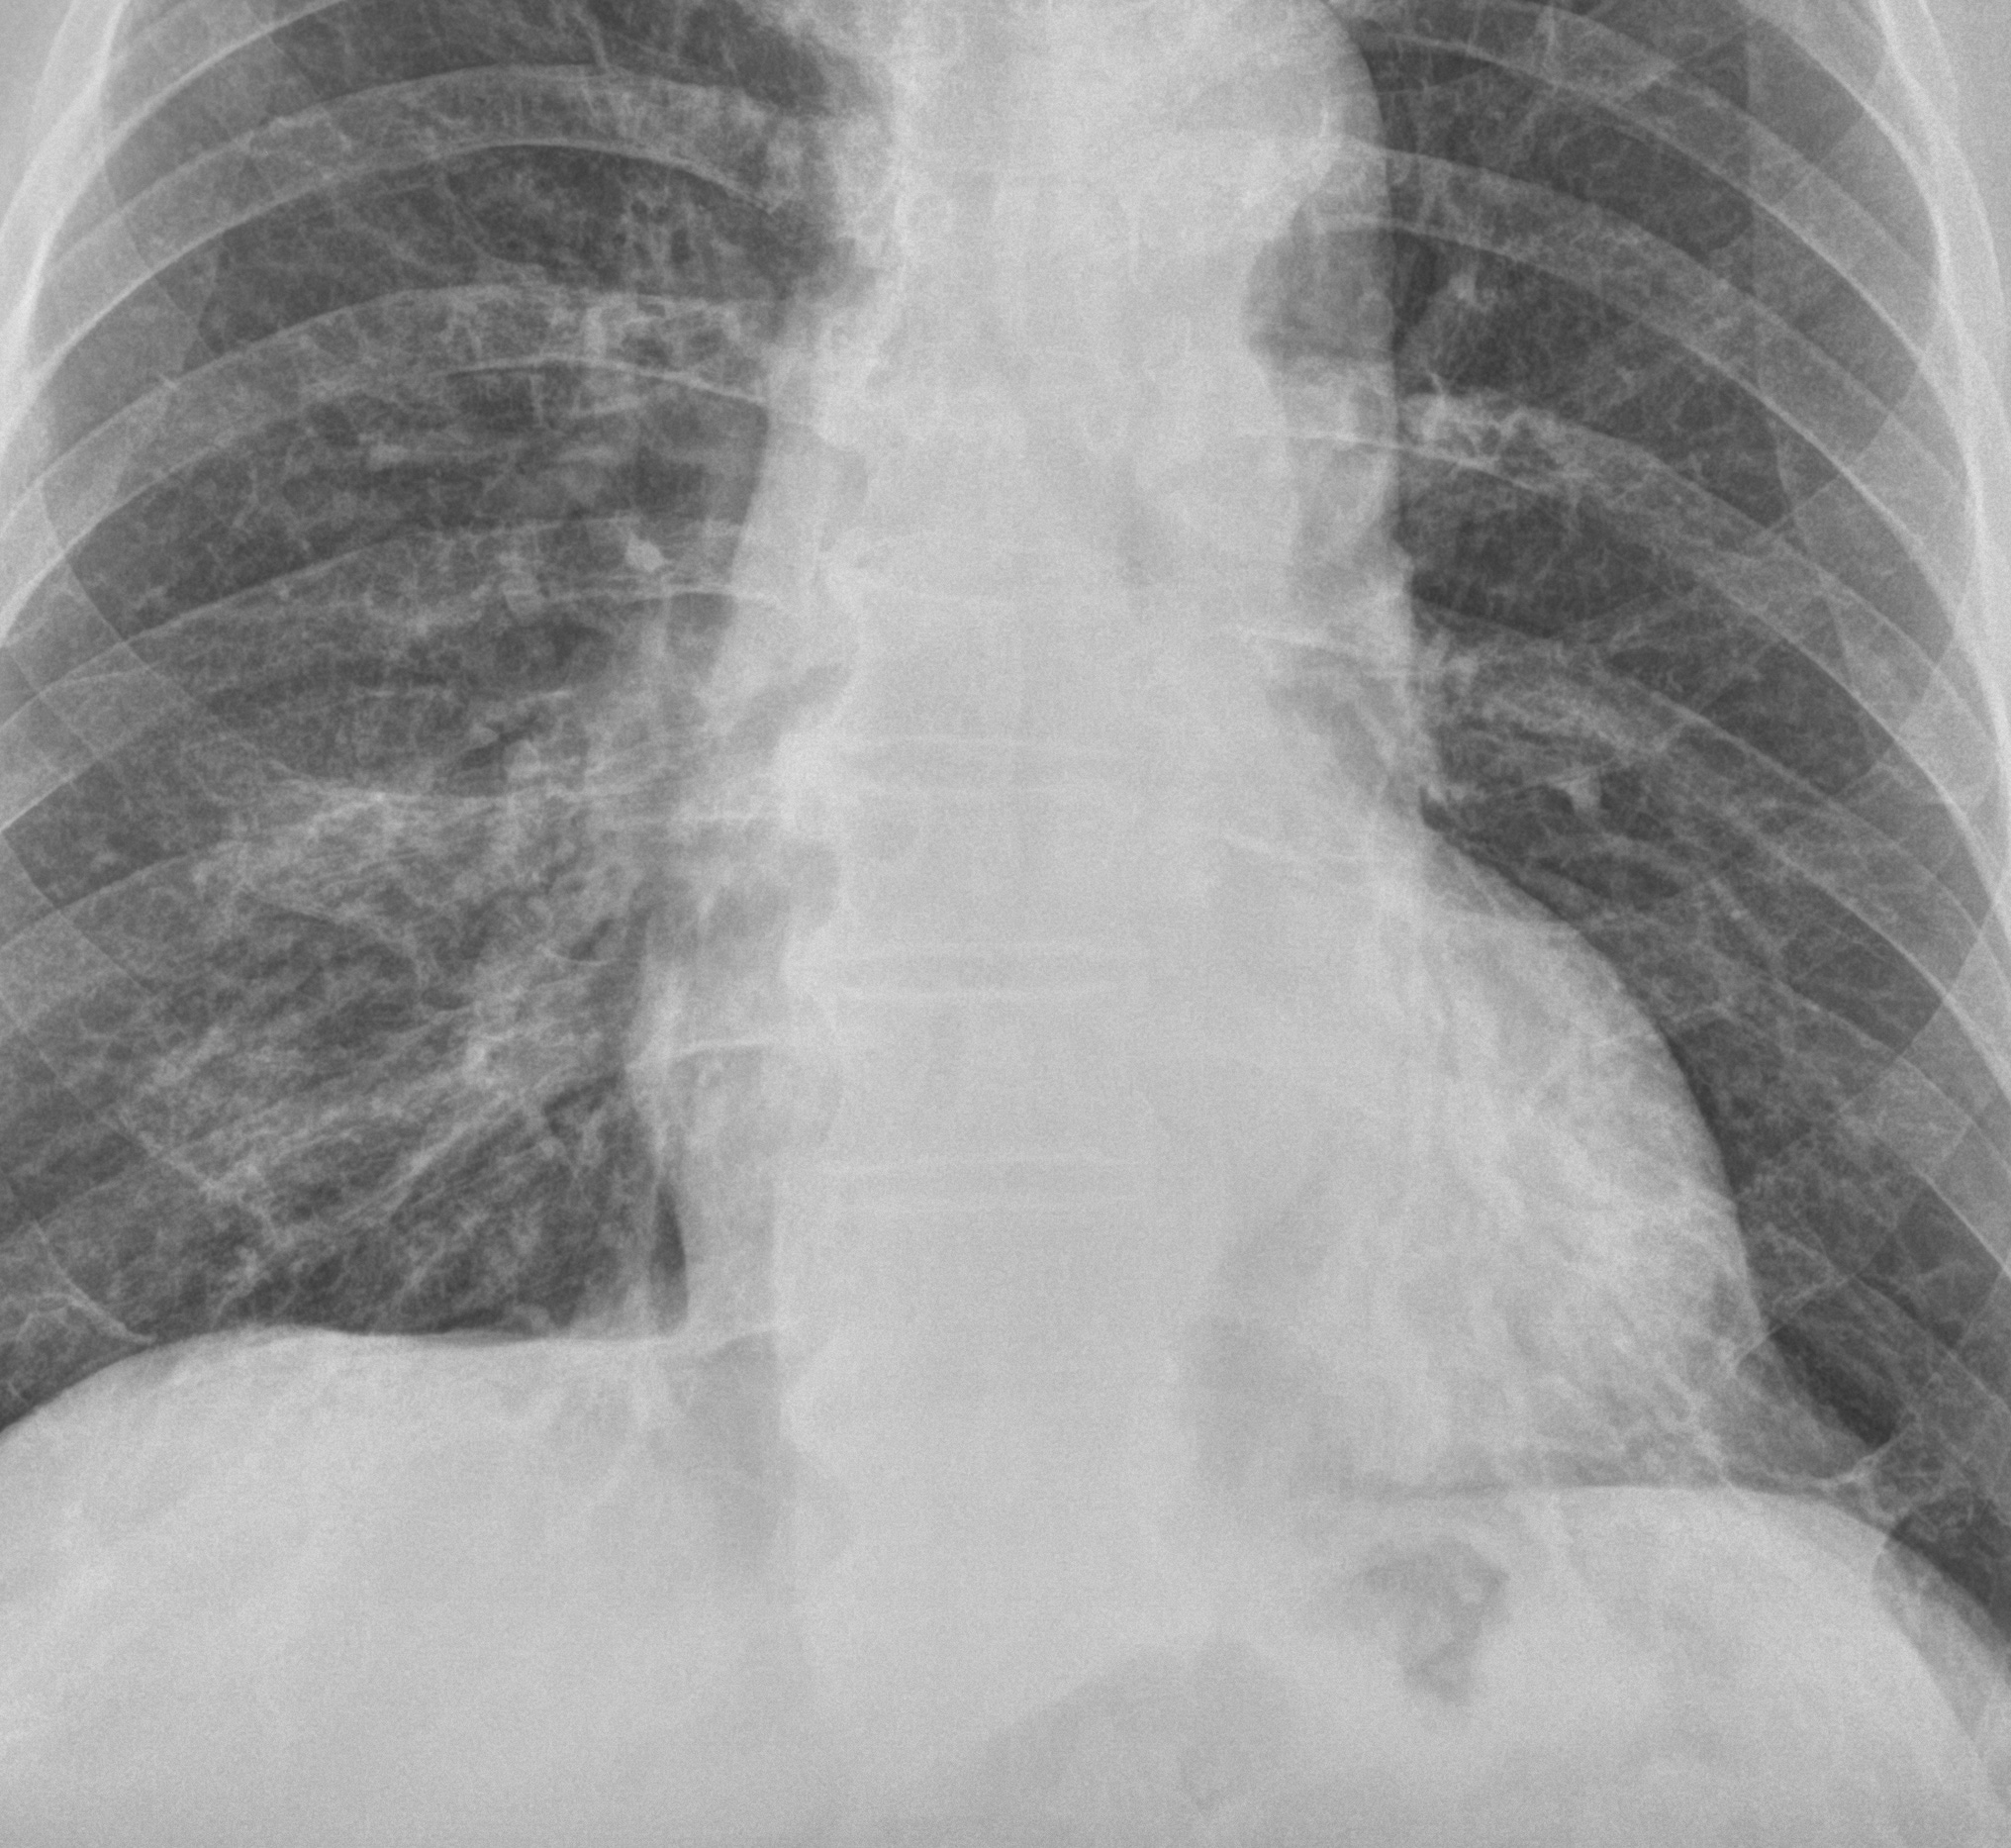

별다른 임상정보 없이 위와 같은 가슴사진이 판독할 리스트에 떳다고 해봅시다. 의학적인 지식이 전무한 일반인이라면, 당연히 이게 뭔지, 뭘 봐야 하는지조차 아무런 감이 없으실 겁니다. 바로 이런 단계를 투자영역에서는 “호구”라고 부를 수 있을겁니다.

사실 이 환자는 동네 의원에서 폐렴이 의심된다고 해서 내과로 입원한 분입니다. 당연히 폐렴의 가능성을 제일 먼저 확인해야 겠지요. 위 영상에서 뭔가 이상소견이 보이시는지요? 의대생이 졸업을 하기 전에 가슴사진에 대해 공부를 할 때 제일 중요하게 강조되는 개념이 “실루엣 징후”입니다. 사실, 의대생이라도 이 실루엣징후라는 것을 “제대로” 공부했다면 이 사진에서 무엇이 문제라는 걸 금방 알 수 있습니다. 어찌 되었든 간에 이게 흉부단순촬영 영상이라는 것, 그리고 환자의 임상증상을 볼 때 왜 이 사진을 촬영한 것인지 전후사정을 이해할 수 있다면 적어도 “뭔가를 좀 아는” 상태라고 할 수 있습니다. 투자영역으로 따지면 호구까지는 아니고 이제 첫걸음을 떼고 앞으로 나아갈 준비가 되있는 “초보”단계로 볼 수 있습니다.

좀 더 심도있게 다루는 경우라면 폐 바깥쪽이나 척추 근처에 위치한 병변에서 나오는 실루엣징후를 언급하기도 하지만, 더 나아가 폐혈관이 가지를 치면서 뻗어가는 모양에 변화가 있는지를 확인하라는 충고를 하는 교과서는 없습니다. 때문에, 이 환자가 폐렴이 의심되는 임상증상으로 내원했다는 정보를 가지고 있는 주치의나 내과의사라 하더라도, 위의 영상에서 어디가 문제가 있다는 걸 짐작하는건 쉽지 않습니다. 다만, 증상이 분명히 있는데 영상에서 뭔가가 나오지 않을 때, “그 다음에는 무엇을 해야 하는지”에 대해서 생각하고 실행에 옮길 줄 안다면, 그것은 최소한 돌팔이는 아니라고 할 수 있을겁니다. 환자분의 증상이 호전되지 않는다면 옆에서 촬영해본다던지, CT를 찍어볼 수 있습니다.

다시 맨 위의 사진으로 들어가서, 심장이 보이는 쪽을 잘 들여다 보면, 심장과 겹치는 부위에서도 폐혈관들이 가지를 치면서 나가는 걸 확인할 수 있습니다. 심장의 뒤쪽으로도 왼쪽 폐가 존재하기 때문에, 당연히 폐혈관이 심장과 겹쳐서 보이는건데, 보시면, 훨씬 안쪽에 보이는 폐혈관 윤곽이 이상하다는게 보입니다. 해부학 지식이 없어도 주변에 가지치며 뻗어나가는다른 혈관들과 윤곽이 다르다는걸 확인하는게 가능합니다.

아직까지 감을 잘 못잡으신 분들에게는 빨간색 화살표가 가르키고 있는 부위입니다. 폐 혈관이라는 게 두께가 일정하게 나가다 가지를 치면서 조금씩 가늘어지는게 정상인데, 해당 부위의 윤곽은 그렇지 않고 곤봉모양처럼 부풀어있거든요. 이건 폐혈관음영 주변에 폐의 공기가 아닌 다른 물질들, 이를테면 가래나 염증성 삼출물, 또는 암세포 같은 다른 물질들이 모여있어서 폐혈관의 윤곽을 가리고 있다는 걸 의미합니다. 이런 현상 또한 “실루엣 징후”라고 할 수 있는데, 실루엣징후에 대해 여기까지 예시를 보여주면서 설명해주는 교과서는 제가 공부하던 때에는 없었습니다.

결국, 이런 영역의 폐혈관 윤곽까지 주의깊게 들여다봐야 한다는 건 의대 졸업을 하고 나서도 영상의학과 공부를 좀 더 심도있게 하거나, 많은 폐렴환자들을 진료하면서 경험을 쌓아야만 알 수 있는 영역입니다. 이렇게 금방 눈에 드러나지 않는 숨겨진 영역들이 이 경우는 심장의 뒷쪽이지만, 여기 말고도 몇군데가 더 있습니다. 영상을 볼 때마다 그런 부분들을 유심히 들여다 보아야 한다는 사실을 경험이나 공부를 통해 잘 알고 있으며, 실제로 그 부분들을 유심히 들여다보는 습관이 되 있는 의사라면, 옆쪽에서 촬영한 영상이나 CT를 굳이 추가하지 않더라도 쉽게 폐렴병변을 확인해서 진단이 가능하며, 앞으로의 치료경과를 판단하는 것도 기본적인 단순촬영을 통해 가능합니다.